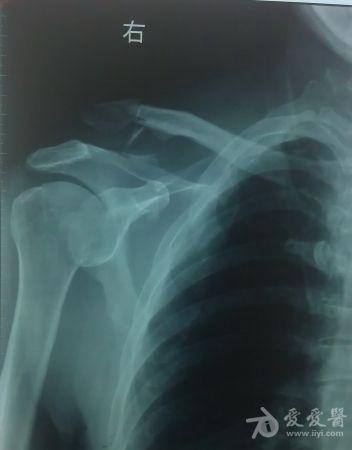

本帖最后由 chen_js 于 2012-10-16 11:24 编辑 患方陈xx,男性,64岁。主诉:锁骨骨折术后三个月,钢板断裂。现病史:因右胫腓骨骨折于2012

年4

月26

日入住xx医院骨科,诊断为:右锁骨骨折、右肩锁关节脱位(图片一)。接受手术治疗,术中使用解剖形接骨板--